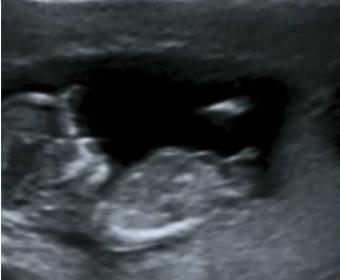

i have this pic to.

Attachment 20231